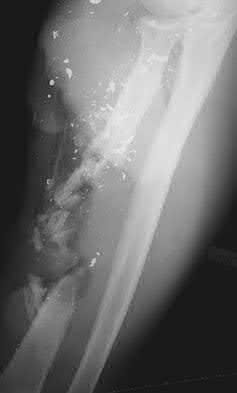

1005) Figure 48 shows the radiograph of a 17-year-old boy who sustained a gunshot wound to his forearm. There is a small entrance wound on the volar surface. The exit wound is dorsal and more than 15 cm in size, with loss of skin and an extensive amount of devitalized muscle hanging out of the wound. Vascular supply to the hand is excellent, the ulnar and median nerves are intact in the hand, but the radial sensory nerve function is absent. After repeated surgical

debridements of the wound and bone, definitive treatment for the fracture would most likely be which of the following?

1. Spanning external fixation of the radius

2. Open reduction and internal fixation of the radius with free fibular flap interposition

3. Open reduction and internal fixation of the radius with interposed strut allograft

4. Open reduction and internal fixation of the radius with massive cancellous allografting

5. Open reduction and internal fixation of the radius with massive cancellous autografting

Corrent answer: 2

The injury needs a very complex traumatic reconstruction. After repeat debridements, there will be a very long segmental loss of the radius, with a significant loss of skin and muscle covering the bone. Spanning external fixation represents a good temporary fixation tool but will not be a definitive solution. The preferred procedure is a vascularized fibular graft with associated skin flap from the lateral leg. This surgical option brings healthy vascularized bone and soft-tissue coverage into an area with significant bone and soft-tissue loss. Placement of large quantities of allograft material, especially strut allograft, is generally contraindicated in the setting of open fractures with soft-tissue compromise because of the risk of infection. Internal fixation and

massive cancellous autografting is usually limited to one defect of less than 5 cm with intact soft-tissue covering.